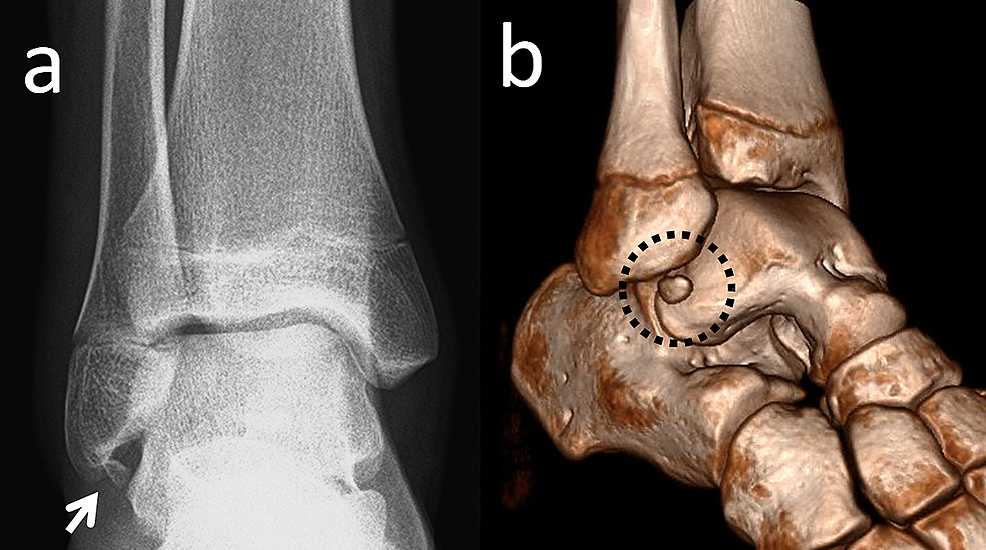

Figure 4 from Rare and common ossicles of the lower extremity Imaging Accessory Ossicles Def Commonly seen at the foot. accessory ossicles are normal variants that are frequently seen but often overlooked or misdiagnosed. accessory bones, also called supernumerary or inconstant bones, are skeletal variations, which can be found as. accessory ossicles are supernumerary and inconstant structures. accessory ossicles of the feet are common developmental variants with almost 40 having been. Accessory Ossicles Def.